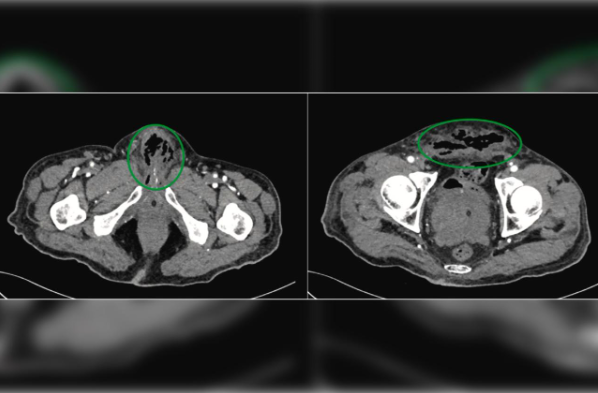

Os exames revelaram que, apesar dos sinais vitais estarem estáveis, o paciente apresentava múltiplos abscessos – nódulos cheios de pus – na próstata e no pênis. Além de antibióticos e insulina, ele recebeu uma transfusão de sangue.

Os médicos inicialmente tentaram preservar o pênis, mas, diante da necrose e decomposição do prepúcio, tiveram que removê-lo antes de realizar a amputação total do órgão. O tecido estava completamente necrosado, resultando na perda total do pênis. Uma semana depois, o idoso recebeu alta do hospital.

A equipe médica que atendeu o paciente relatou no artigo científico que a necrose isquêmica do pênis – uma condição rara que ocorre quando o fluxo sanguíneo para o tecido é reduzido ou interrompido – é incomum devido à rica irrigação sanguínea do órgão. No entanto, quando ocorre, o risco de sepse e complicações graves é elevado.

No caso do paciente em questão, a necrose foi causada por uma combinação de fatores: diabetes tipo 2 mal controlada, doença arterial periférica e a colocação traumática de um cateter transuretral.